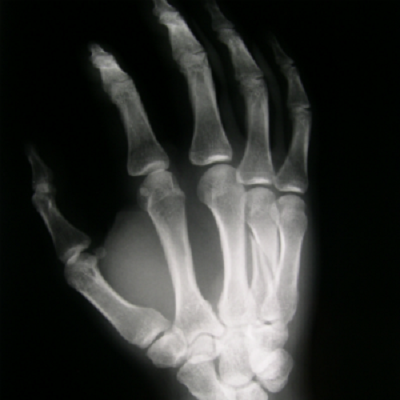

Стартап из Дании Particle3D разработал интересную технологию печати пористых протезов, материалом для которых служит ортофосфат кальция. Сейчас технология уже готова к массовому испытанию на людях.

По их технологии клетки организма как бы обрастают вокруг импланта, превращая его в родную кость. Тестирование на животных показало, что для того, чтобы внутри протезов появились кровеносные сосуды требуется не больше 8 недель.

Инновация Particle3D состоит в том, что протезы в теле пациентов выполняют роль каркаса, на котором организм достраивает поврежденные ткани.

В случае обращения пациента со сломанной костью или какой-либо патологией, достаточно провести сканирование места и отправить полученную модель импланта на шлифовку. Далее имплант можно отправлять в печать и вводить в тело пациента.

Пока Particle3D не удалось сделать импланты столь же крепкими, как настоящие кости. На практике это значит, что пока организм полностью не восстановится — пользоваться поврежденной конечностью можно с ограничениями. Уже сейчас исследователи говорят о большом будущем этой технологии, поскольку она сопряжена с меньшими оперативными вмешательствами в тело пациента и имеет минимальный риск отторжения. Даже современные биоразлагаемые импланты несут в себе риск повторных вмешательств.